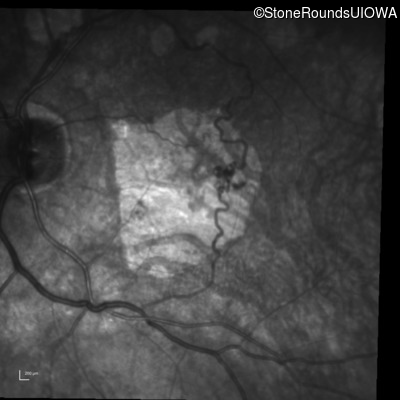

Infrared Fundus Photograph - Right - 20/125 -2

Exemplar

Infrared Fundus Photograph - Left - 20/80